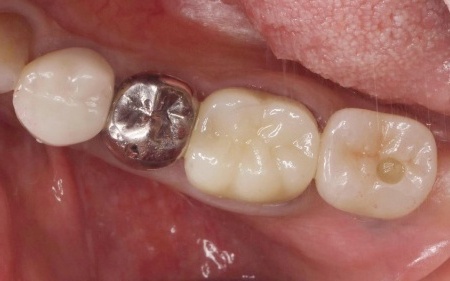

拝見したところ、右上の犬歯には被せ物が装着されていました。

被せ物が装着されていると、レントゲン検査で歯の内部の状態を正確に確認することは困難です。

そこで、原因を詳しく調べるため被せ物を慎重に取り外し歯の内部を確認したところ、歯根が縦方向に割れる「歯根の垂直破折」が認められました。